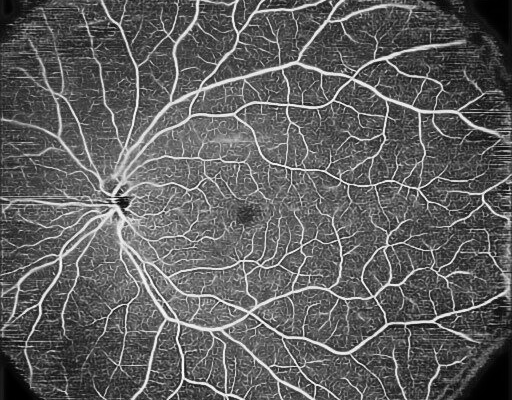

- OCT-Angiografie (optional): Detaillierte Darstellung der Gefässstrukturen mit proprietärem OCTARA™ Algorithmus

Das Swept-Source-OCT Triton bietet eine einzigartige Qualität in der Bildgebung des vorderen und hinteren Augenabschnitts. Mit einer beeindruckenden Brillanz sind die Strukturen von Glaskörper und Aderhaut gleichzeitig darstellbar. Dazu gibt es hochauflösende Fundusbilder, die Darstellung von Blutgefässen ohne Injektion von Kontrastmitteln und in der Variante Plus auch Fluoreszenz-Angiographie und Autofluoreszenz-Aufnahmen.